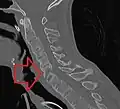

The earliest changes demonstrable by plain X-ray shows erosions and sclerosis in sacroiliac joints. Progression of the erosions leads to widening of the joint space and bony sclerosis. X-ray spine can reveal squaring of vertebrae with bony spur formation called syndesmophyte. This causes the bamboo spine appearance. A drawback of X-ray diagnosis is the signs and symptoms of AS have usually been established as long as 7–10 years prior to X-ray-evident changes occurring on a plain film X-ray, which means a delay of as long as 10 years before adequate therapies can be introduced.[26]

CT scan showing bamboo spine in ankylosing spondylitis